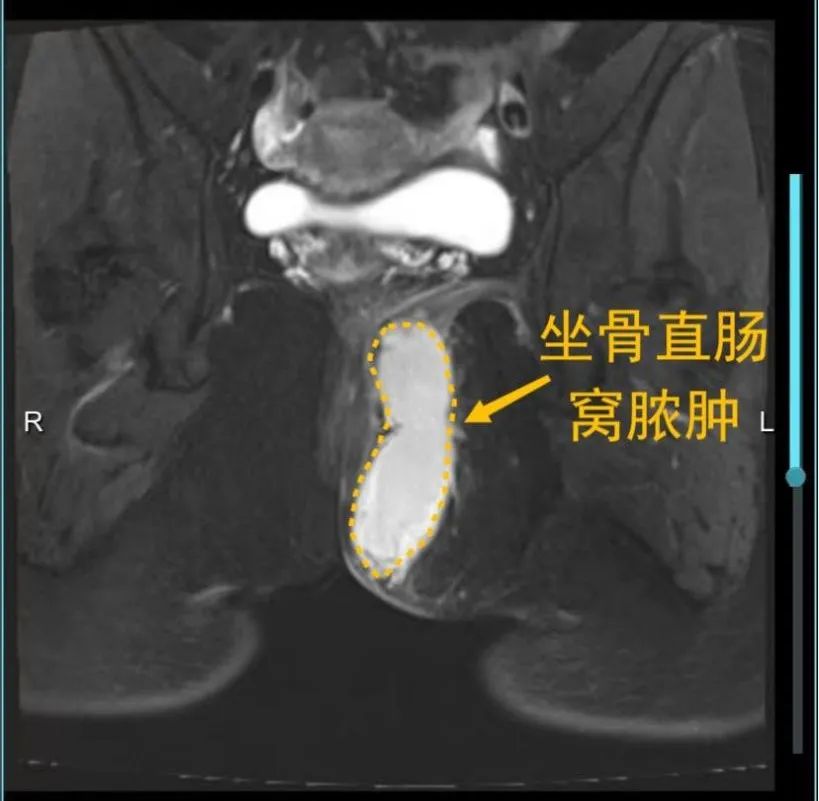

肛周脓肿,又称肛管直肠周围脓肿,中医称为“肛痈”。指肛管和直肠周围软组织内或其周围间隙内发生急性化脓性感染疾病,其症状是肛周持续剧烈疼痛,红肿,并伴有发热,恶寒等表现,其特点是自行破溃,或在手术切开引流后常形成肛瘘。

江西省人民医院肛肠外科治疗肛周脓肿的优势特色

肛周脓肿属于感染性疾病,它是肛肠外科常见病,起病急,一旦确诊,应尽早行手术治疗。江西省人民医院肛肠外科采用中西医结合治疗肛周脓肿,具有独特优势。